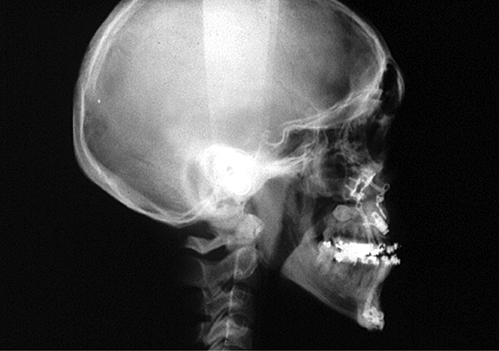

Figure 2: Demonstration of changes to posterior airway space by maxillary

advancement osteotomies. Preoperative (top) postoperative (bottom).

Diagnosis of the level of airway obstruction can be difficult and techniques including sleep nasendoscopy and apneoa graph can be employed. Lateral cephalometric radiographs can be helpful for assessing the posterior airway space and perhaps more accurately 3D CT analysis of the airway can be performed. Mandibular advancement devices when successful can be suggestive of airway obstruction at the level of the tongue base. It is our experience, however, that more severe OSA is usually a multi-level problem and success is more likely therefore with a multilevel solution.